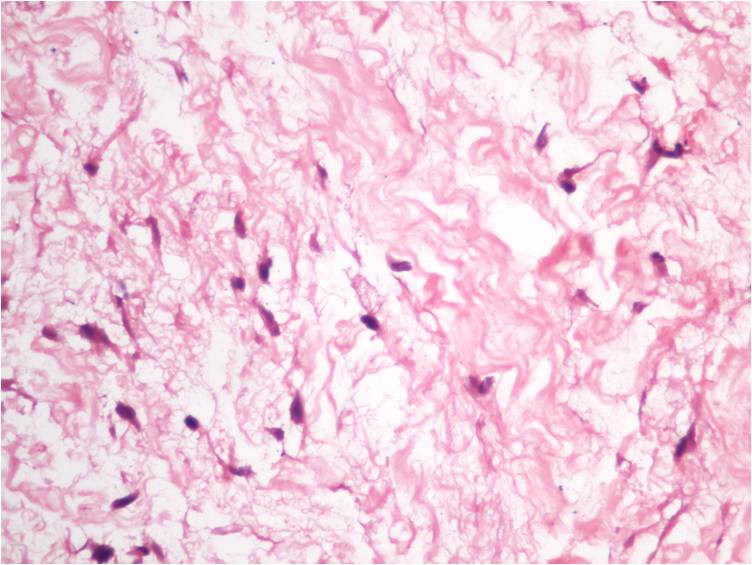

Cytopathology of intramuscular myxoma.

Cytopathology, Intramuscular, Myxoma

2. Choukimath MS, Rangappa PK. Fine needle aspiration cytology of soft tissue tumors with special emphasis on grading of spindle cell sarcomas. International Journal of Applied Biology and Pharmaceutical technology 2012;3:47-60.

3. Silver WP, Harrelson JM, Scully SP. Intramuscular myxoma: a clinicopathologic study of 17 patients. Clin Orthop 2002;403:191-7.

4. Caraway NP, Staerkel GA, Fanning CV, Varma DG, Pollock RE. Diagnosing intramuscular myxoma by fine-needle aspiration: a multidisciplinary approach. Diagn Cytopathol 1994;11:255-61.

5. Åkerman M, Rydholm A. Aspiration cytology of intramuscular myxoma: a comparative clinical, cytologic and histologic study of ten cases. Acta Cytol. 1983;27:505-10.